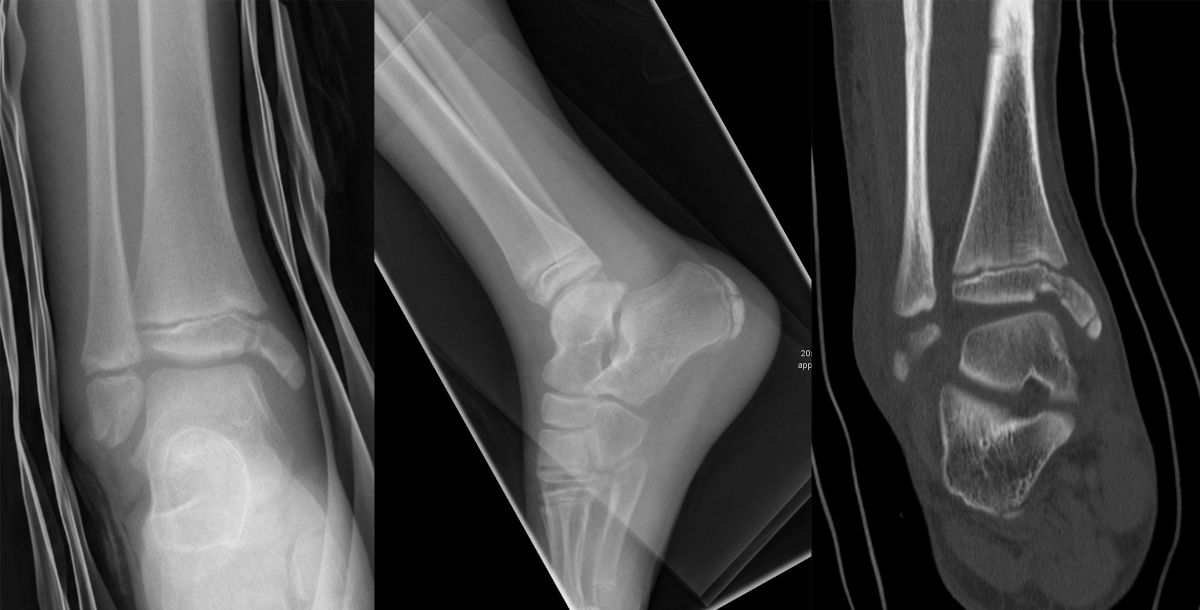

Rein epiphysäre Frakturen werden als Twoplane-Frakturen bezeichnet. Der Frakturverlauf liegt in der Epiphyse und dem noch nicht verknöcherten Anteil der Wachstumsfuge. Gibt es noch einen zusätzlichen metaphysären Keil handelt es sich um eine Triplane-Fraktur. Bei einer Triplane-Fraktur kann sich in Einzelfällen die metaphysäre Fraktur bis in die Epiphyse fortsetzen, sodass eine zusätzliche Querfraktur resultiert. Es entsteht der Eindruck eines zusätzlichen hinteren Volkmann Fragments.

• Twoplane-Fraktur: Epiphysäre Fraktur, welche epiphysär und durch den noch nicht verknöcherten Teil der Fuge verläuft (Aitken II Verletzung bei einer teilweise mineralisiert Wachstumsfuge).

• Triplane-I-Fraktur: Epiphysäre Fraktur, mit teilweisem Verlauf durch die Wachstumsfuge und gleichzeitigem metaphysären Keil.

• Triplane-II-Fraktur: Epiphysäre Fraktur, mit Verlauf durch die Wachstumsfuge. Der metaphysäre Keil setzt sich in die Epiphyse fort, was zu einer weiteren quer verlaufenden Frakturlinie im Gelenk führt.

In Abhängigkeit vom Reifezustand der Wachstumsfuge kann der epiphysäre Frakturspalt sehr weit medial bis ganz lateral zu liegen kommen. Ein sehr weit lateral liegender Frakturspalt entspricht funktionell nahezu einem knöchernen Ausriss der vorderen Syndesmose, was sich im Röntgenbild an einer erweiterten Malleolengabel erkennen lässt 9

Der teilweise komplexe Frakturverlauf bei Übergangsfrakturen lässt sich im CT zuverlässig darstellen 10. Der erfahrene Untersucher kann bereits mit Röntgenaufnahmen des Sprunggelenks in zwei Ebenen in Verbindung mit zwei 45° Schrägaufnahmen sehr umfassende Aussagen zum Frakturverlauf treffen (v. Laer 2013), die Präzision und Aussagekraft der Computertomografie ist aber zweifelsohne überlegen und wird von den meisten Behandlern bevorzugt 11, auch wenn sich zu diesem Thema in der Literatur eine teilweise sehr emotional geführte Diskussion findet. Einigkeit hinsichtlich der Indikation für ein Schnittbildverfahren besteht bei Triplane-Frakturen, wenn Zweifel darüber bestehen, inwieweit die metaphysäre Fraktur den tragenden Gelenkanteil tangiert 12.